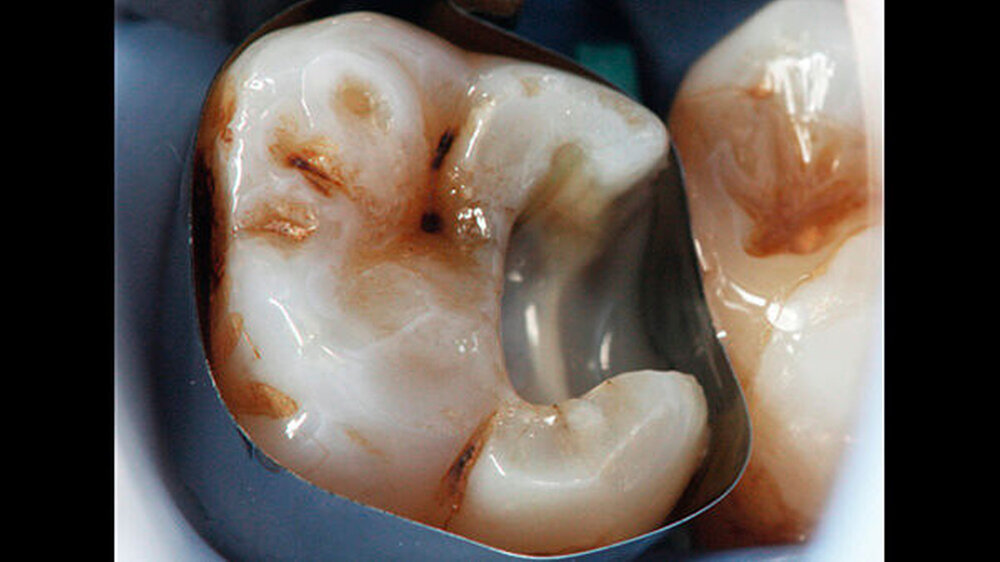

Bei der vollständigen Kariesentfernung kam es nicht zu einer Freilegung der Pulpa (Abbildung 3). Anschließend wurde eine Metallmatrize (HaweTofflemire Matrize, Kerr Dental) angelegt und verkeilt. Die Kavität wurde gereinigt und getrocknet.

Das Zementmaterial wurde nach Herstellerangaben angemischt und mittels eines kleinen Kugelstopfers (Dycal-Instrument) im Bereich der distalen pulpalen Wand appliziert und mit einem Heidemann-Spatel adaptiert. Das Material wurde damit gleichzeitig sowohl zur Caries-profunda-Behandlung als auch zur Unterfüllung eingesetzt. Nach einer Abbindezeit für das Material von zwölf Minuten wurde der Defekt mit einer Kompositfüllung restauriert (Abbildung 4).